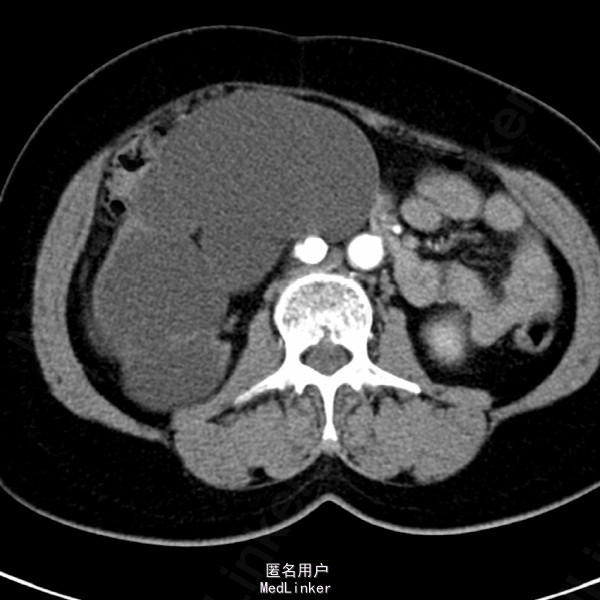

患者女,62岁11月,因“体检发现右肾积水4天”入院。自诉无任何不适。

超声检查示:1.右肾重度积水 2.右肾结石,疑右侧输尿管起始端结石 SPECT肾显像示:右肾无功能;左肾GFR代偿性增高,左上尿路引流通畅。

诊断:右输尿管上段结石 右肾重度积水无功能。行腹腔镜右肾切除术。术中见患者右肾实质菲薄,体积较大,与周围组织粘连重,穿刺吸出淡黄色尿液约1200ml。